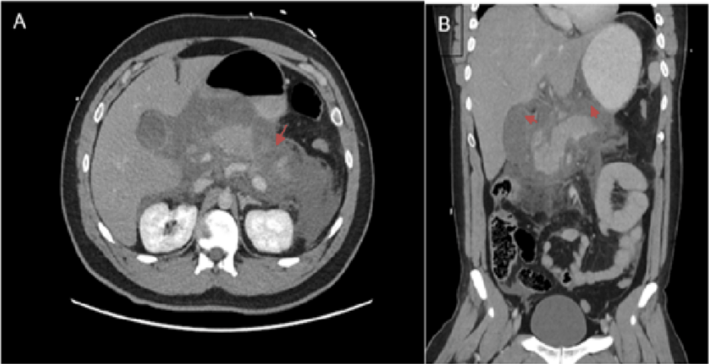

fasciotens®Abdomen wurde bei einem Patienten mittleren Alters mit schwerer Peritonitis nach einer Dünndarmperforation eingesetzt.